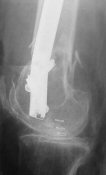

Attached are few examples from our Hospital:

B. Fixation loosening: distal cutting of the nail, non-unions do happen (cases attached).

Locking Plating has more distal screws than any nail, fixed angles and provides much better fixation, especially in osteoporotic bone.

A new toy is more interesting and fashionable. And anyway it is not panacea, i have already seen presentations with LISS failures like the attached one presented by D.Seligson. And people also demonstrated incisions say that the method is not so LESS invasive as it supposed to be.